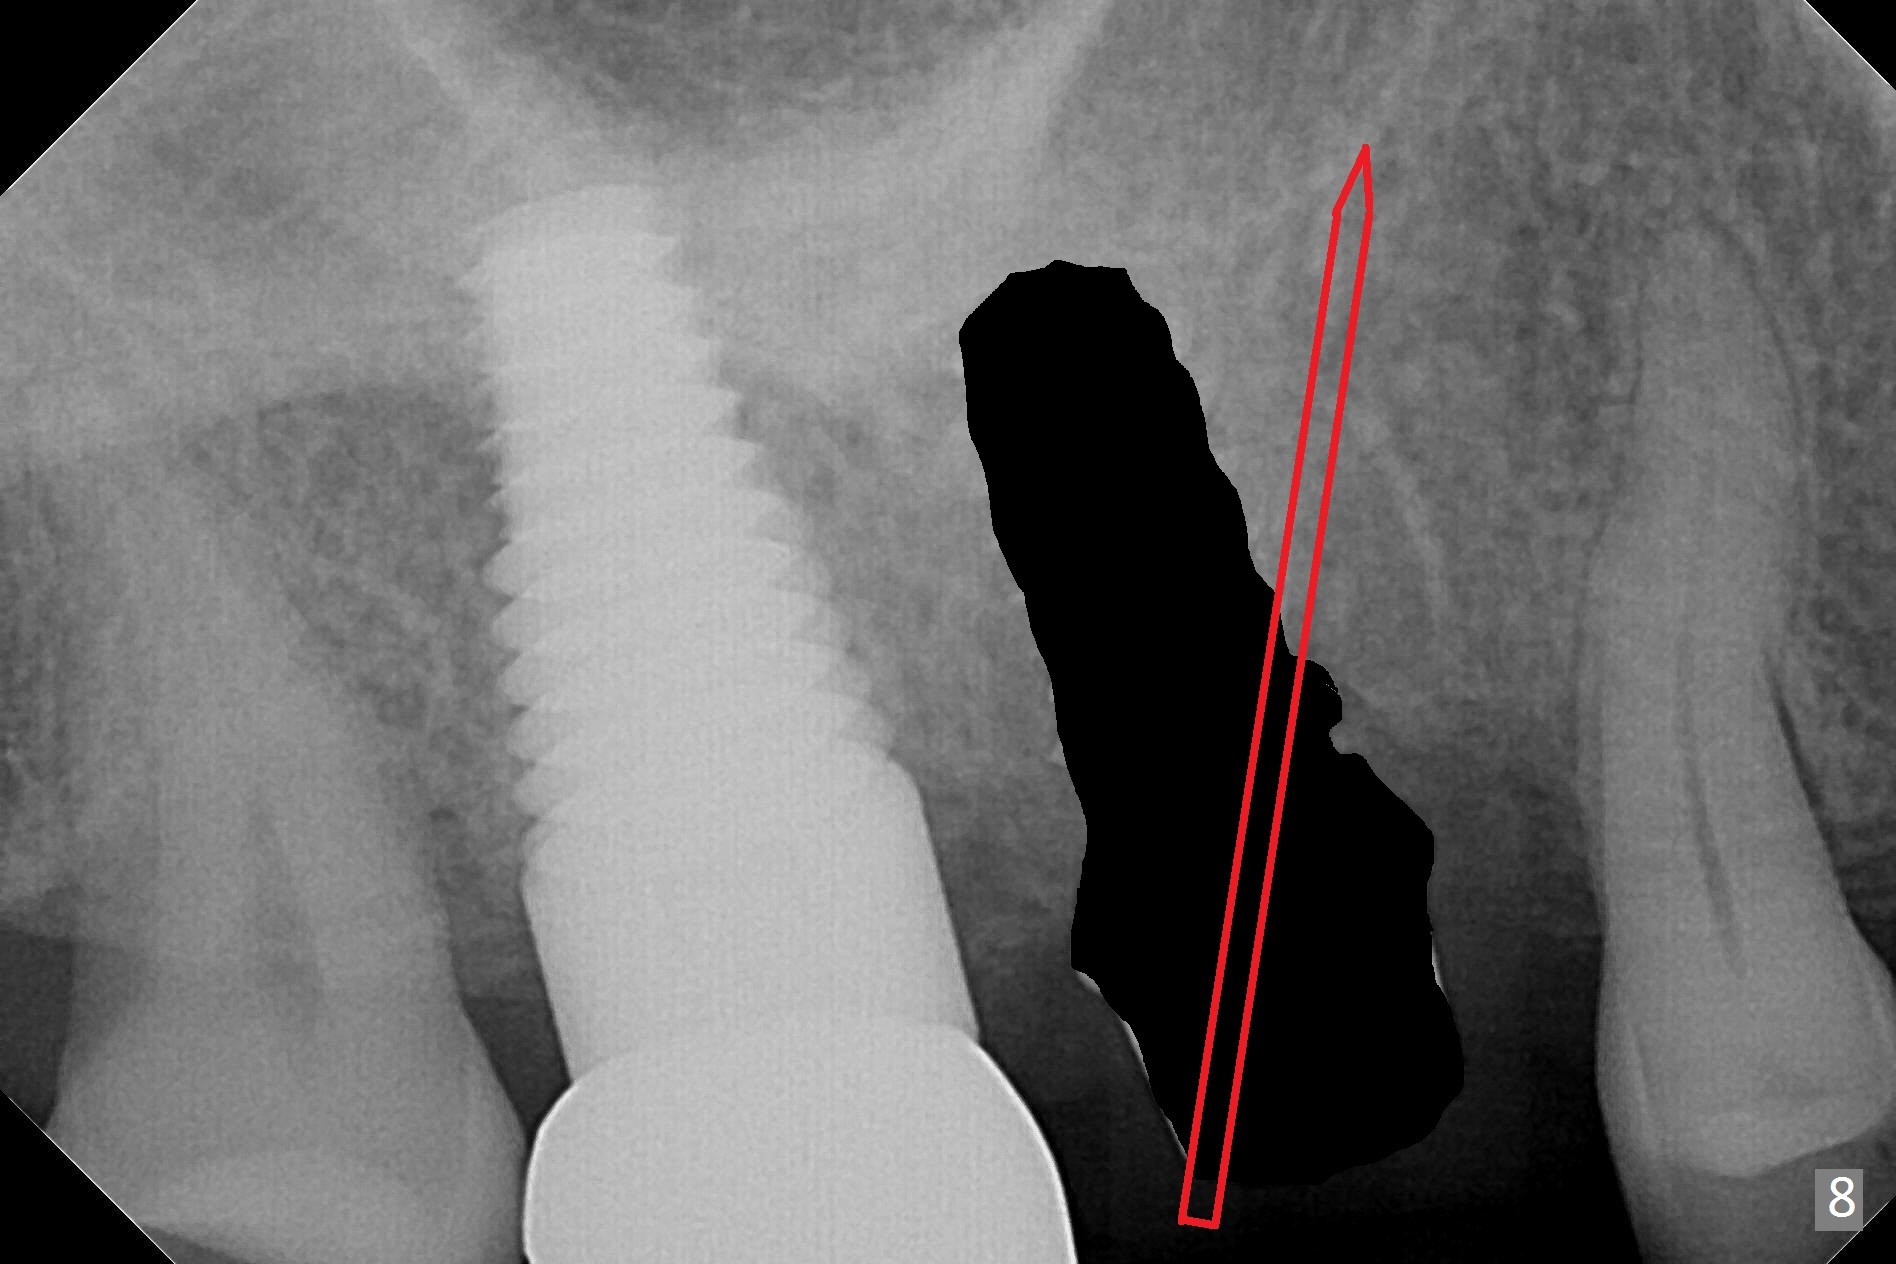

The patient returns with chief complaint of crown is loose with pain 3 months postop (Fig.7). Under local anesthesia, the provisional is removed. The gingiva is erythematous. The implant has mobility. A healing abutment is placed (6x2 mm). One month later, the implant remains unstable. The patient is scheduled to return 3.5 months postop to either retighten the implant with healing screw or replace with a 6x17 mm Tatum implant (Fig.9) after changing trajectory (Fig.8 red arrow).